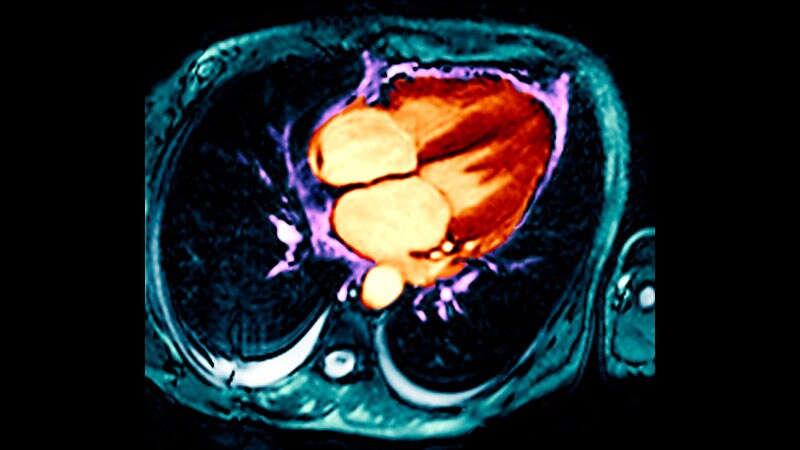

EXCEL at 5 Years: PCI, CABG 'Relatively Comparable' in LM DiseaseWhich of PCI or CABG for left main disease better prevented death, MI, or stroke? One prevailed early on, the other after

a few years. Overall, they matched. The clinical message has shades of gray.